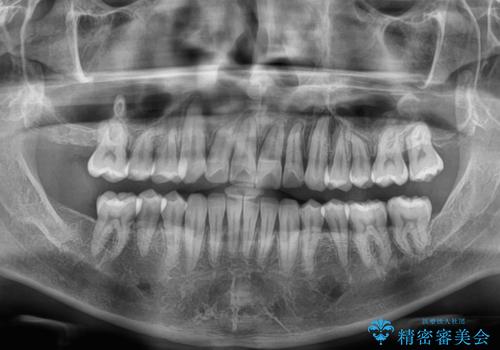

- 上下前歯のデコボコを気にして来院された患者様です。

ワイヤー矯正でもマウスピース矯正でも可能でしたが、短期間で、自身の手を煩わせることなく治療を行いたいとのことで、ワイヤー装置にて矯正治療を行うこととしました。

上顎前歯の舌側転位が顕著であったため、治療期間が長くなると思われましたが、僅か1年で無事に終えることができました。